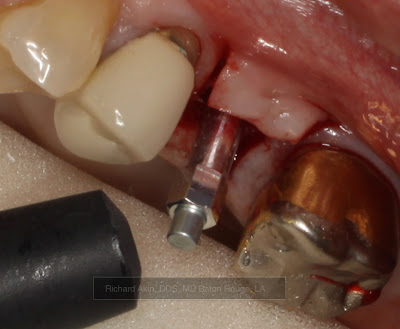

Trabecular Metal Implant Insertion: Site #14

Patient is a 67 year old female with a history of pharmacologically controlled hypertension and hypothyroidism.

Tooth #14 was removed approximately 6 months previously due to the presence of pain and a firm buccal alveolar swelling of 2 month duration. Due to the anatomic position of the zygomatic process in this patient, plain radiography was of minimal diagnostic value. Cone beam CT confirmed periradicular pathology. Root fracture was suspected preoperatively and was confirmed the day of tooth removal.

The large defect was grafted with mineralized particulate allograft using a guided bone regeneration technique.

Patient was treatment planned for a dental implant at site #14 with a closed sinus lift after a 6 month healing period.

Preoperative coronal cone beam image of tooth #14 demonstrating a large well contained periapical lesion along the floor of the maxillary sinus.

6 month postoperative periapical radiograph illustrating the appearance of the grafted area.

At surgery, bone was noted to be dense (D1).

Final sinus lift osteotome used to depth (~13mm).

4.7mm x 11.5mm Zimmer Trabecular Metal Implant.

Implant insertion torque value was greater than 35 Ncm.

Osstell reading was taken to determine implant stability.

Osstell ISQ implant stability value was 75 at insertion.

(For reference, implants that are ready for final restoration will typically have an ISQ value of 65 or greater.)

Implant at final depth.

Palatal tissue was contoured to accept healing abutment using a rotary tissue punch.